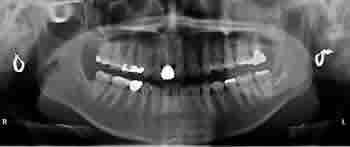

親知らず症例 ①

CT写真